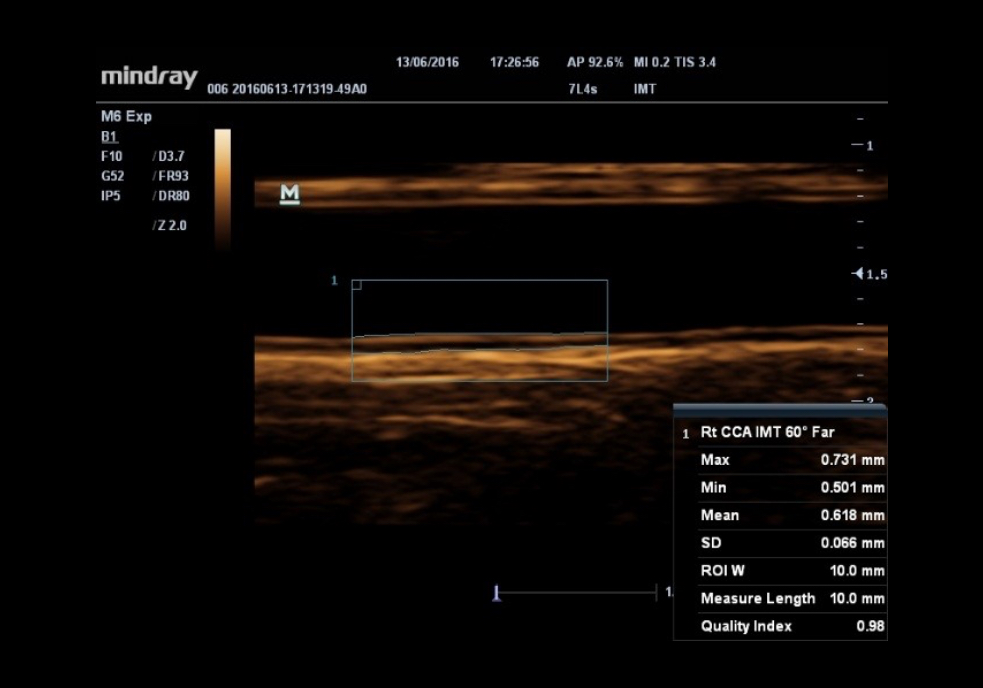

IMT (Grosor ?ntima-Media)

Automedición de grosor de pared anterior y posterior proporcionando un estado preciso de la carótida.